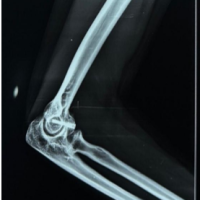

Hip disorders in the paediatric population (patients <16 years) represent a varied collection of conditions ranging from traumatic, developmental, infectious, neoplastic, and metabolic causes [1]. These pathologies, if not promptly diagnosed and treated, frequently result in long-term morbidity, including permanent deformities, chronic pain, gait abnormalities, and compromised quality of life in adulthood [1,2]. The unique developmental anatomy of the pediatric hip, characterized by the presence of a vulnerable physeal plate and changing vascular patterns, contributes to its susceptibility to specific age-related diseases [3]. Common non-traumatic paediatric hip disorders include developmental dysplasia of the hip (DDH) (Fig. 1), Legg-Calvé-Perthes disease (Perthes’) (Fig. 2 and 3), slipped capital femoral epiphysis (SCFE) (Fig. 4), and infective conditions such as septic arthritis (Fig. 5) and tubercular arthritis [3].

Figure 4: Left slipped capital femoral epiphysis.